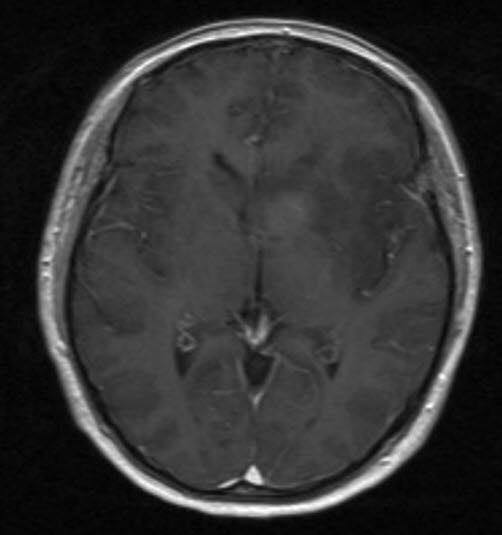

Anaplastisk astrocytom, aksialt snitt

Anaplastisk astrocytom WHO grad III

Gjengitt med tillatelse av Radiologisk avdeling, Universitetssykehuset Nord-Norge